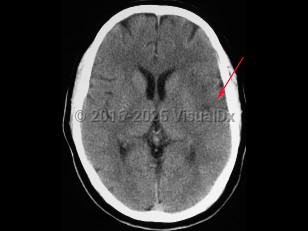

- Intracerebral hemorrhage – Bleeding directly into the brain parenchyma secondary to hypertension, trauma, bleeding disorders, aneurysm rupture, illicit drug use, or vascular malformations. Patients typically present with the gradual onset of symptoms over hours to days with headache, nausea, vomiting, and altered levels of consciousness. If the source of the hemorrhage is from the low-pressure side of the circulation, then the onset of symptoms is more likely to be gradual than if the source is from the high-pressure, arterial side, where symptoms can be quite abrupt in onset. Patients can also present with seizure.

- Subarachnoid hemorrhage – Bleeding directly into the cerebrospinal fluid (CSF) within the subarachnoid space that surrounds the brain due to either an arterial aneurysm at the base of the brain or bleeding from vascular malformation at the pial surface. Onset of symptoms is typically acute with a severe widespread headache, radiation of pain down the neck and back, and vomiting. Meningismus may be present.